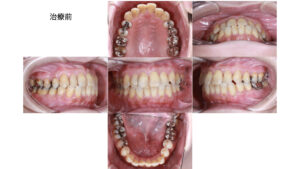

叢生(歯並びのガタつき)に対する矯正治療 — 症例:50代女性

- 主訴:前歯のガタつき(叢生)が気になる

全顎的な虫歯の治療と、歯並びの改善でご相談をいただきました。かねてから、前歯の叢生について悩んでおられ、今回気になるところを全て治療したいという思いで来院されたのことです。

本症例は、非抜歯での治療が可能と判断し、マウスピース矯正(インビザライン)を主体に、一部でブラケットとワイヤーを併用して仕上げを行いました。年齢的な背景と審美的希望を踏まえ、歯の移動量を最小限に抑えつつ安定した咬合を目指しました。

模型分析・セファロ分析の結果、骨格的な問題はわずかで、口元の突出等による改善は不要と判断しました。年齢・歯周状態を考慮し、抜歯を回避した非抜歯矯正が適応と判断しています。

※本症例ではインビザライン単独だと一部前歯の動きが不十分だったため、ブラケット+ワイヤーで補助して理想的な配列に仕上げています。

矯正治療を行うことで、見た目の改善だけでなく、前歯の叢生(ガタガタ)が解消される事で、磨き残しが解消され虫歯や歯周病のリスクも軽減することができました。

また前歯も咬合に参加する事で、臼歯(奥歯)への負担も軽減されています。

審美だけでなく、口腔機能も改善、向上することができました。